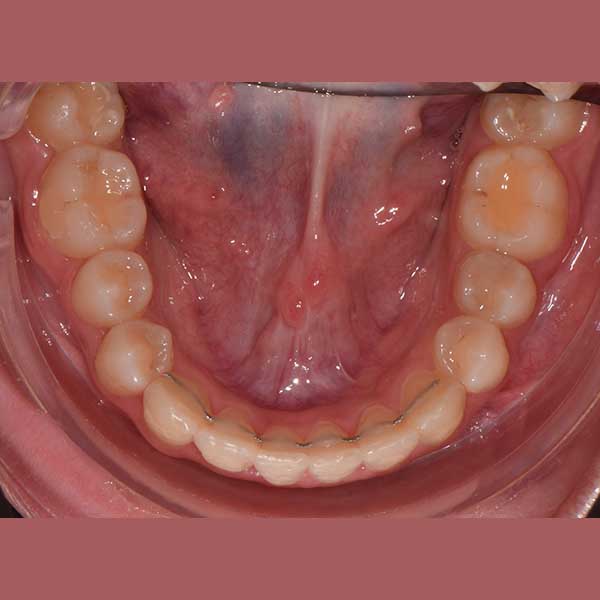

لحسن الحظ، وبعد دراسة الحالة، أكد الدكتور خالد الكاتب أن العلاج ممكن دون الحاجة للقلع. تم اختيار تقويم الدايمون (ذاتي الربط)، لما له من قدرة ممتازة على المساعدة في توسيع الفكين وتحريك الأسنان بفعالية لتوفير المسافة المطلوبة. سمحت هذه التقنية بحل الازدحام وإنزال الناب المرتفع إلى مكانه الصحيح.

النتيجة النهائية:

كما تظهر الصور، نجحنا في رصف الأسنان بشكل ممتاز وتحقيق إطباق مثالي. عاد الناب المرتفع إلى مكانه الطبيعي ضمن ابتسامة متناسقة وجميلة، مما أعاد لمراجعتنا الثقة والسعادة بابتسامتها.